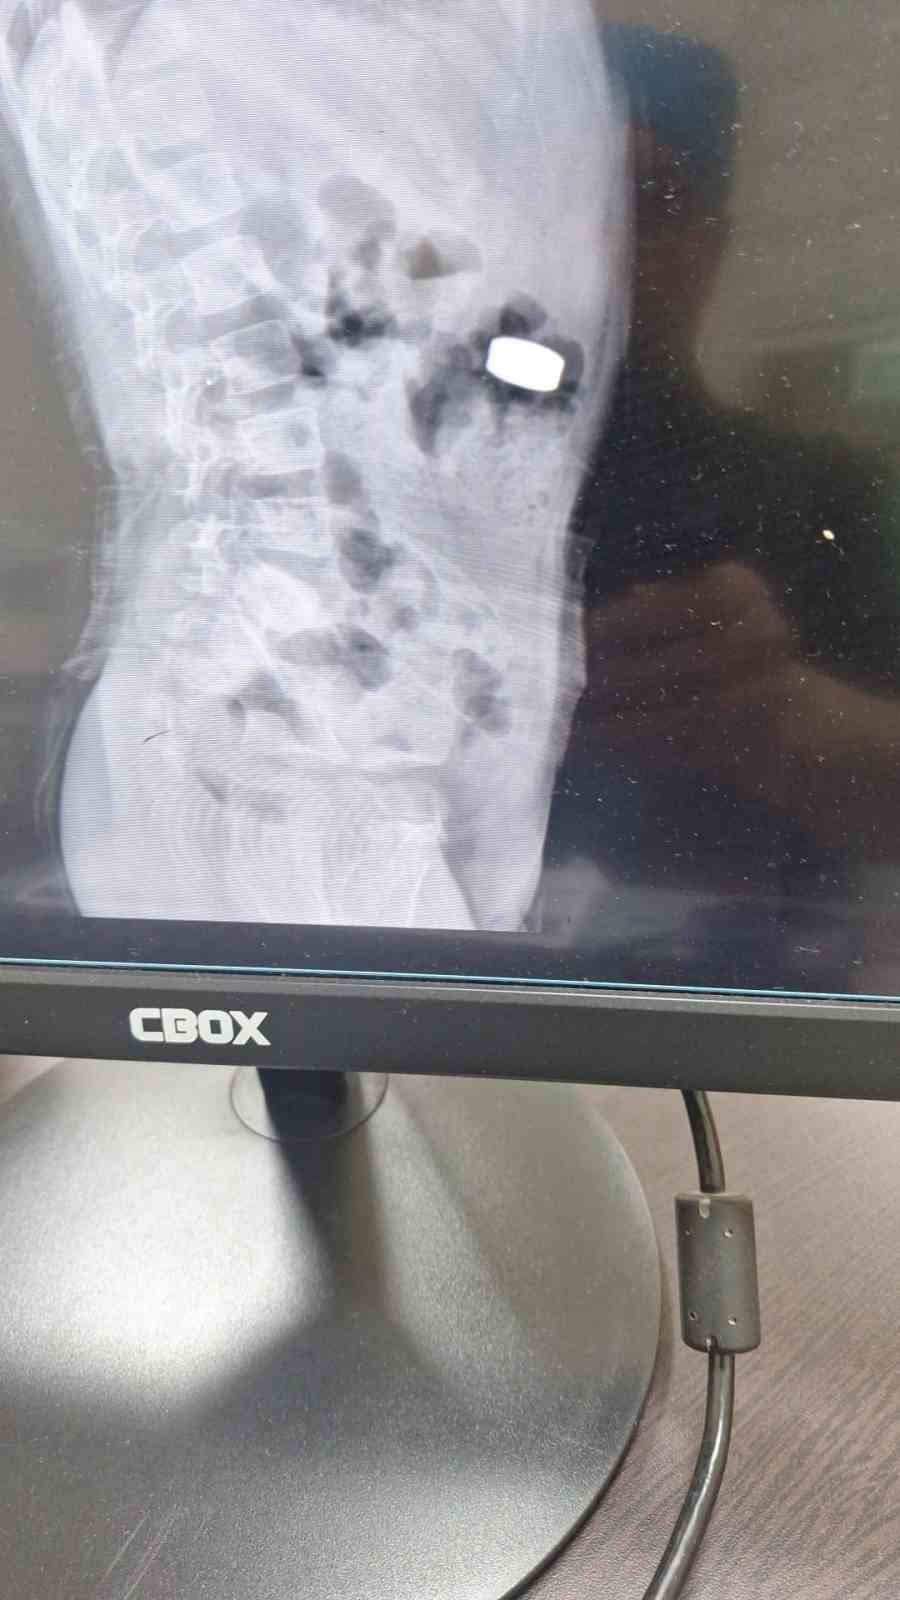

Karaman’da 4 yaşındaki İ.K.’nin mıknatıs yuttuğundan şüphelenen ailesi, Karaman Eğitim ve Araştırma Hastanesi Acil Servisi’ne başvurdu. Yapılan tetkiklerde çocuğun ince bağırsağında iki adet mıknatıs bulunduğu tespit edildi. Gözlem altına alınan çocuğun sağlık durumu 5 gün boyunca takip edildi. Çocuk Cerrahisi Uzmanı Doç. Dr. Mehmet Uysal’ın gerçekleştirdiği operasyonla bağırsakta tıkanıklığa yol açan iki mıknatıs başarılı bir şekilde çıkarıldı.

Hastayı 5 gün boyunca takibe aldıklarını belirten Doç. Dr. Mehmet Uysal, gözetim süresince çekilen filmlerde mıknatısların yer değiştirmediğini söyledi. Uysal, “Hastayı genel anestezi altında ameliyata aldık. İnce bağırsakta iki mıknatısın birbirine yapışık halde olduğunu gördük. Gerçekleştirdiğimiz operasyonla mıknatısları çıkardık. Ameliyat sonrası hastamız üçüncü gününde taburcu edildi. Şu an genel durumu iyi” dedi.